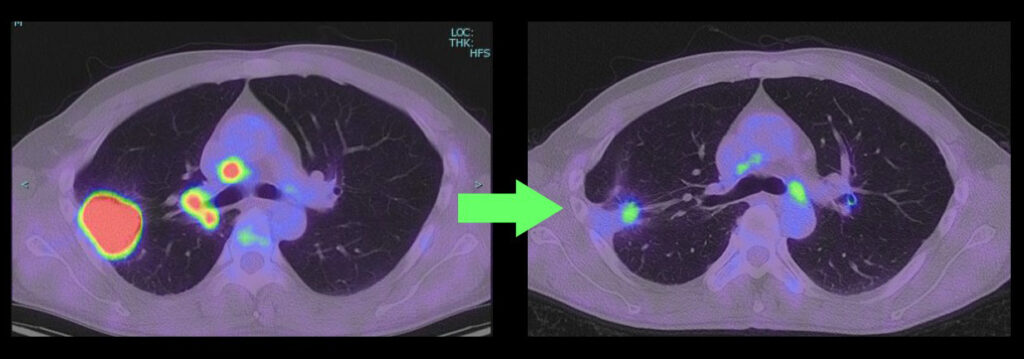

【症例1】下図左)右上葉の病変は胸壁に接し肺門と縦隔リンパ節転移もあり cT3N2M0 IIIB期。はじめから手術を行うと胸壁操作や血管・気管支形成等を要する複雑手術となる可能性がある。免疫チェックポイント阻害剤併用化学療法後、右)腫瘍や転移リンパ節がほぼ消失し通常の上葉切除でわずかに残った病変を摘出して完全切除し得た。(同様の病態で同様の結果を保証するものではありません。)

【症例2】下図左)右上葉の大きな病変が縦隔に近接し一部が縦隔側へ浸潤する。cT4N0-1M0 IIIA期相当と考えられ、この時点でも手術は可能であるが、はじめから手術を行うと大きな開胸による右上葉切除と縦隔隣接臓器の合併切除が見込まれる。免疫チェックポイント阻害剤併用化学療法後、右)腫瘍がほぼ消失し胸腔鏡による低侵襲アプローチで右上葉切除のわずかに残った病変を摘出して完全切除。(同様の病態で同様の結果を保証するものではありません。)